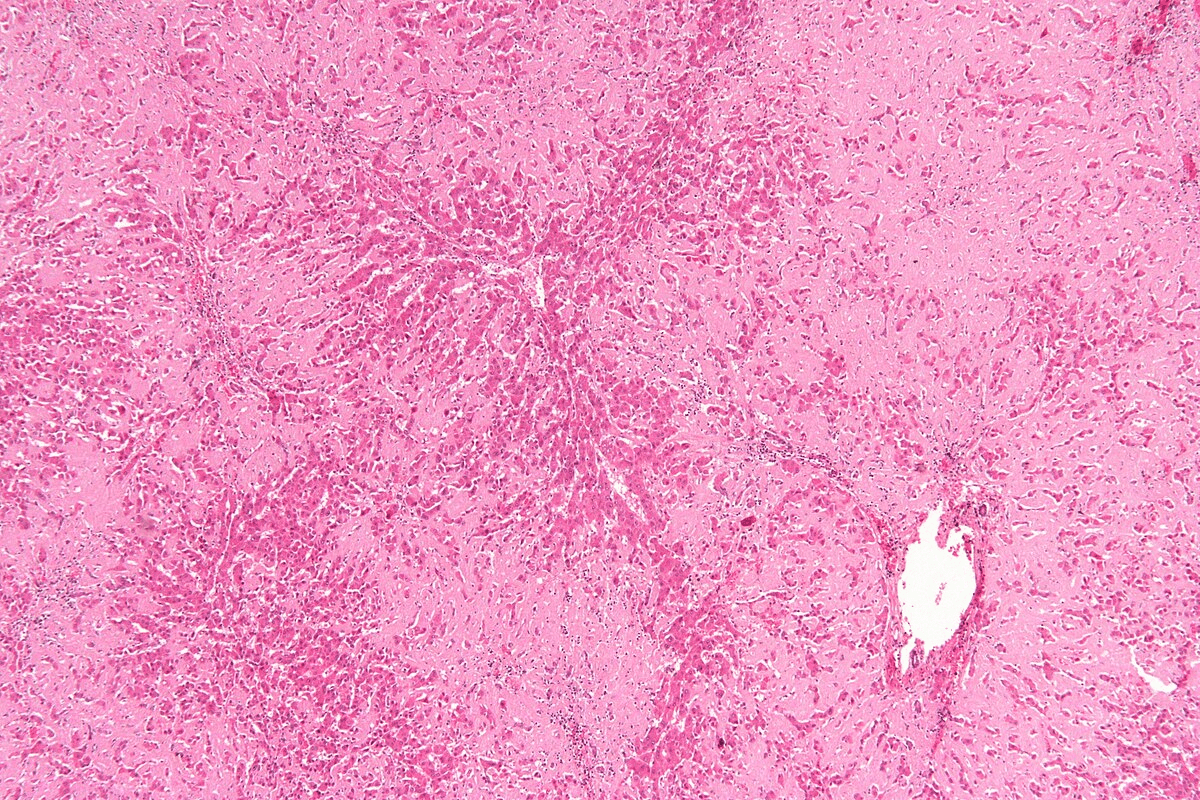

AL amyloidosis is a systemic disorder. It involves the buildup of amyloid fibrils made of immunoglobulin light chains. This condition is often hard to diagnose early, leading to poor outcomes due to multiorgan involvement.